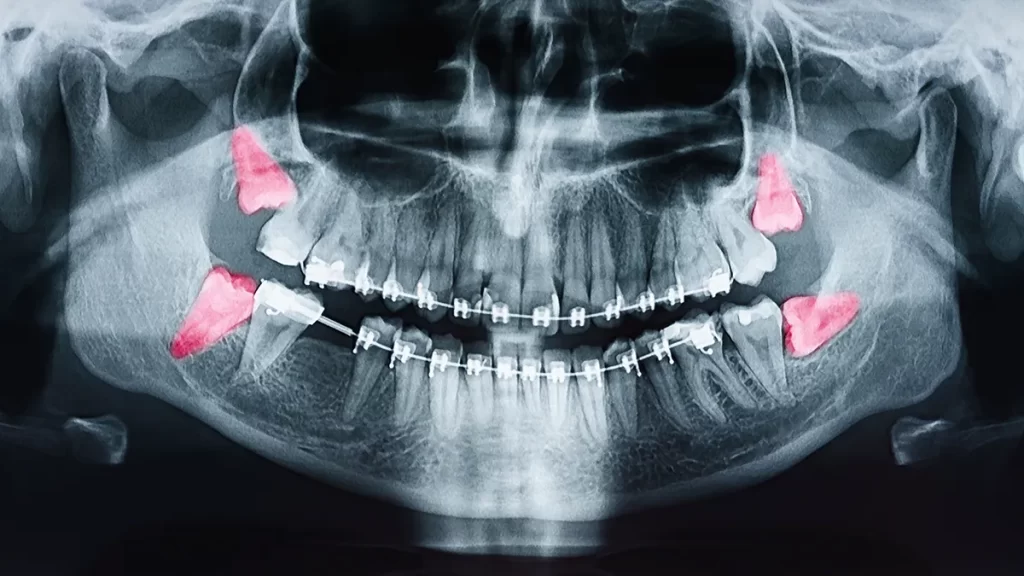

Full mouth x-ray with wisdom teeth highlighted in pink.

Is it time for you or your child to have their wisdom teeth removed? It can be a scary thing, especially since those involved often require going under anesthesia and won’t remember anything a few hours after the procedure. Wisdom teeth are usually removed to prevent damage to teeth in the future, as many patients’ wisdom teeth grow at an angle that negatively impacts their gums, jawbone, or other teeth. It’s also best to get this surgery when you are younger because as you grow older, more complications can arise from the surgery. However, some patients never need to get their wisdom teeth removed due to their wisdom teeth growing in correctly! If you or your child’s wisdom teeth are starting to grow, it might be time for a check-up with us at Emergency Dental Services so we can plan the next steps of action, whether that is surgery or something else!

Wisdom teeth, also known as third molars, are the last to emerge in the back of the mouth. They typically appear in their late teens or early twenties. While some people have no issues with their wisdom teeth, others may experience pain, infections, or other dental problems. In some cases, wisdom teeth may need to be removed to prevent complications or overcrowding in the mouth. It’s essential to have regular dental check-ups to monitor the development and condition of wisdom teeth.